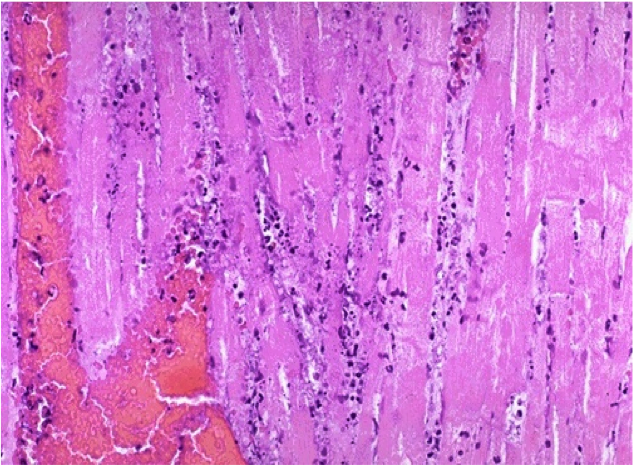

This shows an MI 1-2 days after the infarct.

there is coagulative necrosis of the myocardium

it is difficult to see the striations & the intercalated discs

looks like wavy fibers (b/c of the tension b/w the good fibers & bad fibers)